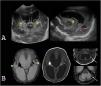

Macrocephaly is a clinical term defined as an occipitofrontal circumference more than two standard deviations above the mean. It is present in 5% of children and is a common indication for imaging studies. There are multiple causes of macrocephaly; most of them are benign. Nevertheless, in some cases, macrocephaly is the clinical manifestation of a condition that requires timely medical and/or surgical treatment. The importance of imaging studies lies in identifying the patients who would benefit from treatment. Children with macrocephaly associated with neurologic alterations, neurocutaneous stigmata, delayed development, or rapid increase of the circumference have a greater risk of having disease. By contrast, parental macrocephaly is predictive of a benign condition. Limiting imaging studies to patients with increased risk makes it possible to optimize resources and reduce unnecessary exposure to tests.